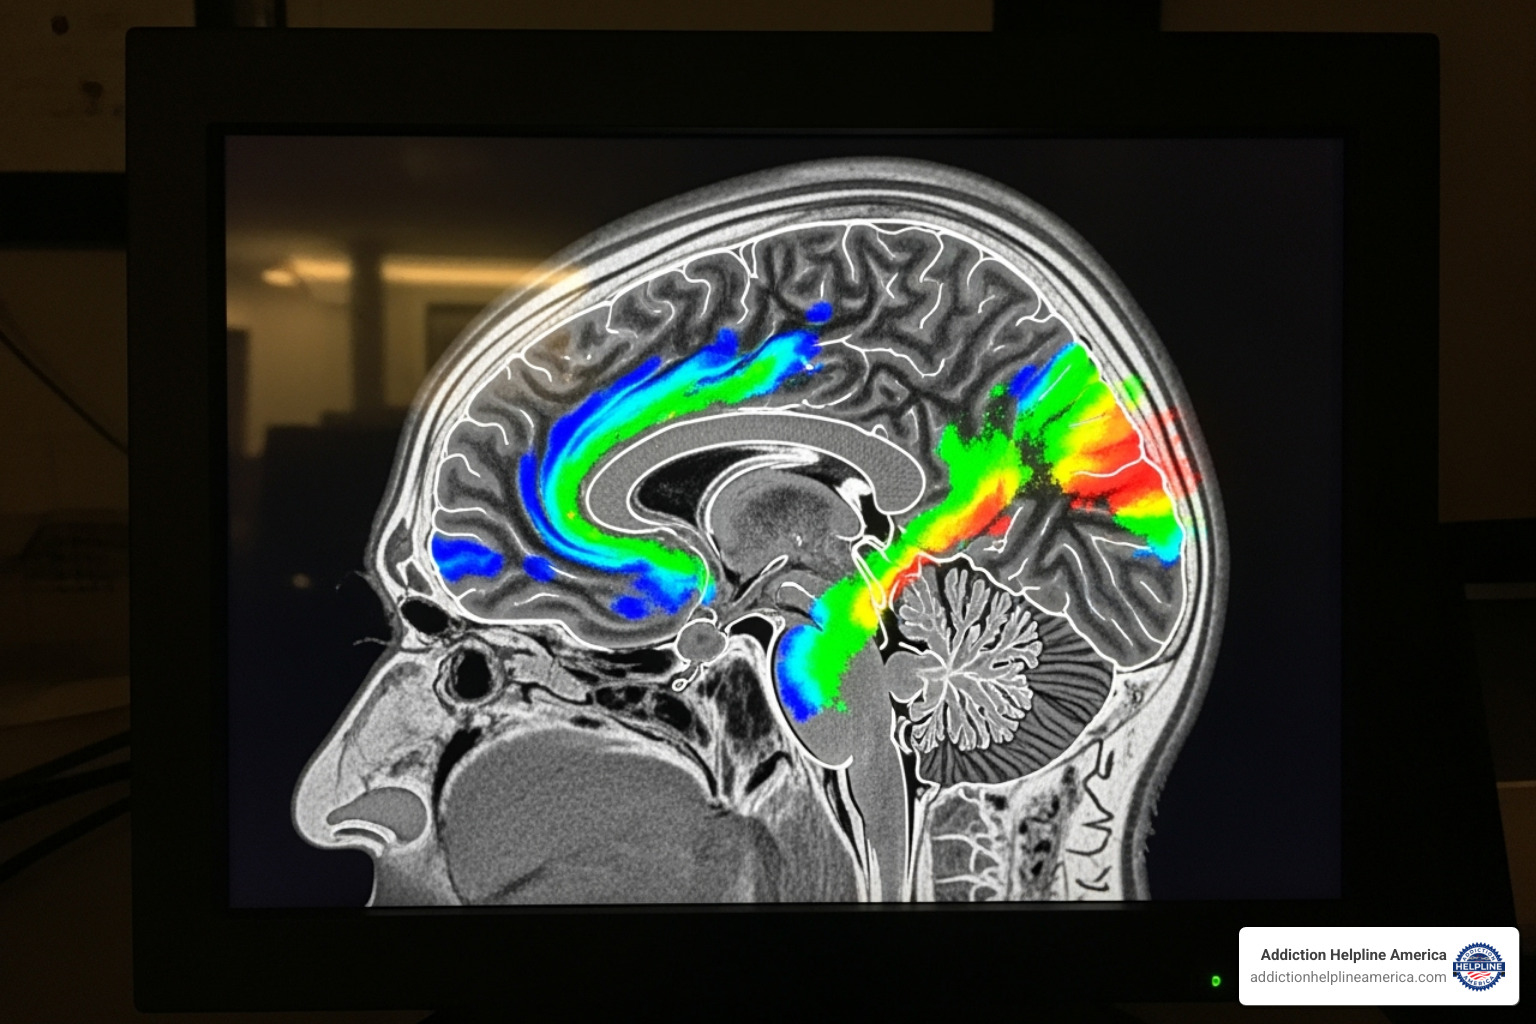

Cocaine floods the brain with dopamine, the “feel-good” chemical, creating an intense rush far beyond natural rewards. To protect itself, the brain reduces its own dopamine production and receptors. This creates a cruel trap: without the drug, the person can barely feel pleasure from normal activities.

As addiction hijacks the brain, it becomes convinced it needs cocaine just to function. Tolerance builds rapidly, meaning more of the drug is needed for the same effect, and intense cravings and psychological dependence take hold with frightening speed.